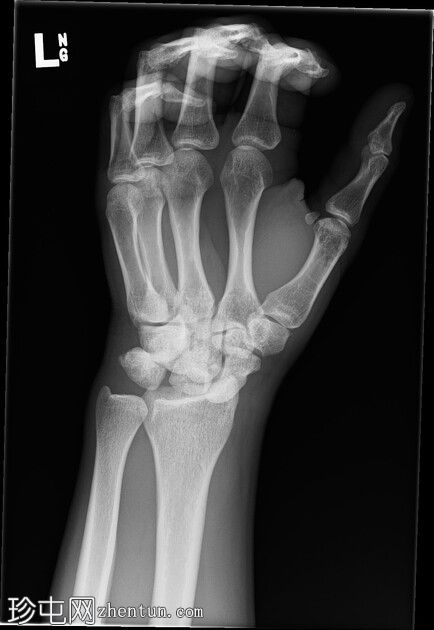

左腕

X光片

正面

斜位

侧面

前后位:舟月骨间隙明显增宽,月骨呈三角形。侧面显示月骨掌侧脱位,头状骨和桡骨远端保持正常排列,符合月骨脱位。陈旧性背侧三角骨骨折。腕部软组织肿胀。